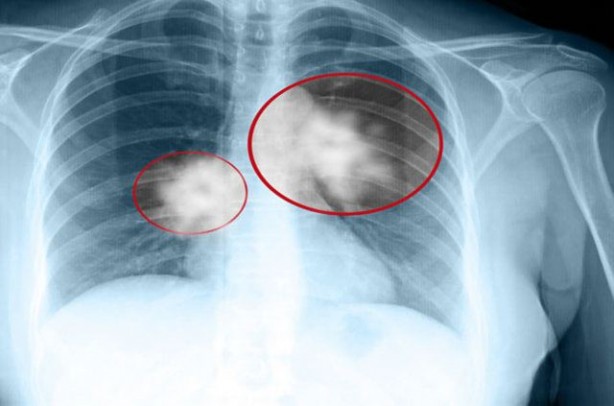

Akciğer kanseri hem erkeklerde hem de kadınlarda en sık ölüm nedeni. Sinsi bir şekilde ilerleyen akciğer kanseri bazen belirti vermese de işte dikkatten kaçmaması gereken akciğer kanseri belirtileri... Dünyada ve ülkemizde hızla yaygınlaşan akciğer kanseri erkeklerde prostat, kadınlarda ise meme kanserinden sonra en sık görülen ikinci kanser türü olarak tanımlanıyor. En önemli nedeninin sigara olarak gösterildiği akciğer kanseri; özellikle nefes darlığı, hırıltı, ani kilo kaybı ya da çeşitli ağrılarla kendini gösterebiliyor.